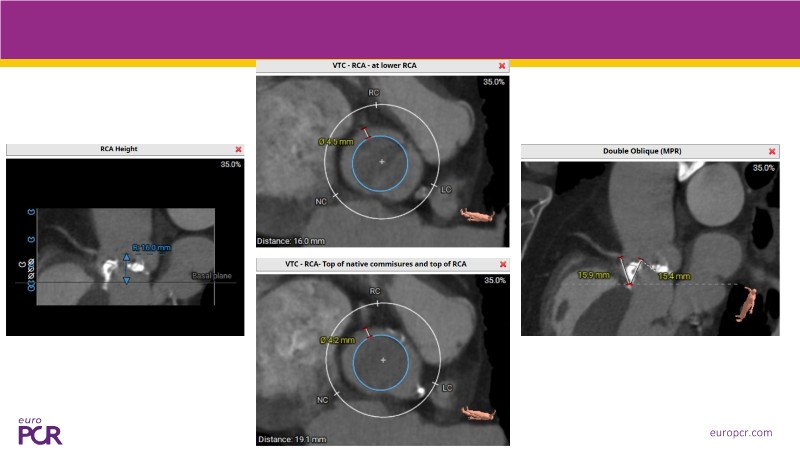

This session presents the latest updates on the novel Myval Octapro transcatheter heart valve (THV), based on one year of real-world clinical experience. Experts share practical tips and clinical cases that highlight how this innovative device can improve TAVI patient outcomes. The session also addresses imaging and sizing strategies critical for TAVI planning, as well as procedural best practices for successful implantation of the Myval Octapro THV.

- To learn from the experts best-in-the-class TAVI practice: pre-procedural (imaging, sizing rationale, treatment strategy), procedural tips and tricks and post-procedural management